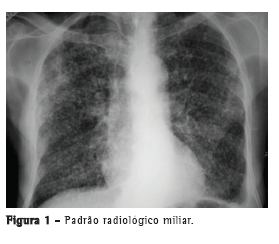

Com relação aos achados radiológicos, infiltrados reticulares e consolidação são os padrões mais frequentes,(5,6,10,15,17) sendo que cavitação pode estar presente em 27-50% dos casos.(6,10,16) As Figuras 1 a 4 mostram alguns dos principais padrões radiológicos nesse contexto.

Os pacientes com tuberculose e necessidade de cuidados intensivos podem evoluir para síndrome da angústia respiratória aguda (SARA). A incidência descrita de SARA é variável: 12,1%,(10) 13,4%,(15) 28,1%(5) e, em alguns estudos, até mais de 60%.(6,16) Em uma série de casos com 15 pacientes hospitalizados com tuberculose e insuficiência respiratória, apesar das características clínicas e radiológicas compatíveis com SARA, os achados histopatológicos foram compatíveis com broncopneumonia tuberculosa, sem evidência de SARA.(7) Em um estudo no Brasil, as alterações histopatológicas pulmonares encontradas em autopsias de pacientes que evoluíram a óbito por insuficiência respiratória aguda foram revisadas, e o principal padrão associado com tuberculose foi o dano alveolar difuso.(11)

O tempo entre o início dos sintomas e o início do tratamento antituberculose descrito nos estudos foi maior do que 30 dias em 28,8-34,0% dos casos.(6,17) O tempo entre a admissão e o início da terapêutica adequada foi avaliado em apenas um estudo, sendo relatada uma média de 4,3 dias. Naquele estudo retrospectivo, o tempo entre a admissão e o início do tratamento foi menor nos pacientes com tuberculose miliar do que naqueles com pneumonia tuberculosa (2,8 ± 2,5 dias vs. 5,0 ± 7,0 dias; p = 0,048).(16) Pode haver atraso no diagnóstico e, consequentemente, no começo do tratamento pela difícil diferenciação radiológica entre pneumonia tuberculosa e pneumonia bacteriana grave. Considerando essa dificuldade na distinção entre as duas patologias, um estudo avaliou as diferenças nas características clínicas e radiológicas de pacientes com pneumonia grave com e sem tuberculose internados em UTIs. A história de sintomas com duração maior do que duas semanas e a presença de micronódulos ou de padrão cavitário na radiografia de tórax foram significativamente associados com tuberculose pulmonar ativa.(20) Adicionalmente, o padrão miliar na radiografia de tórax também pode ser erroneamente interpretado como insuficiência cardíaca congestiva.(18)